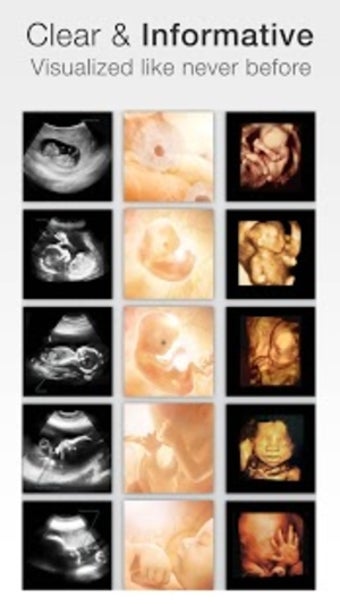

아기의 발달과 진행 상황을 추적하고 손끝에서 올바른 정보를 얻을 수 있는 좋은 방법입니다.